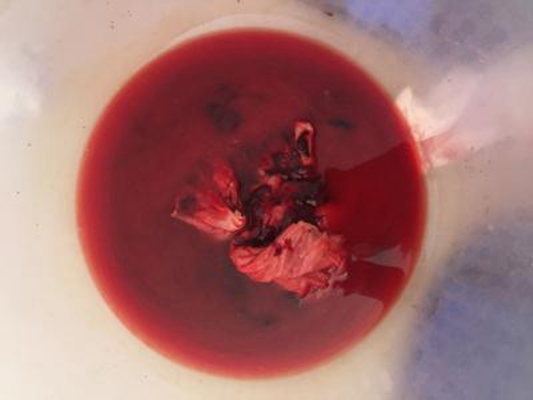

流產圖片

流產掉下來的孕囊

流產掉下來的孕囊

流產掉下來的孕囊

流產掉下來的孕囊

流產掉下來的孕囊

流產掉下來的孕囊

流產掉下來的孕囊

流產掉下來的孕囊

流產掉下來的孕囊

流產掉下來的孕囊